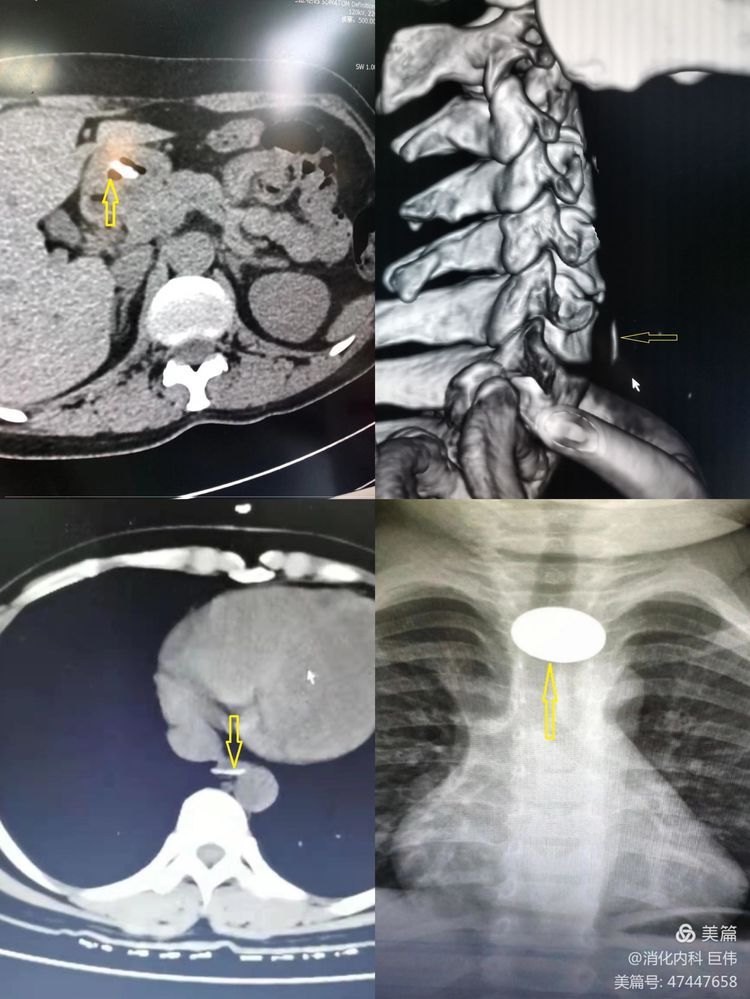

一、影像学明确异物位置及嵌顿情况: